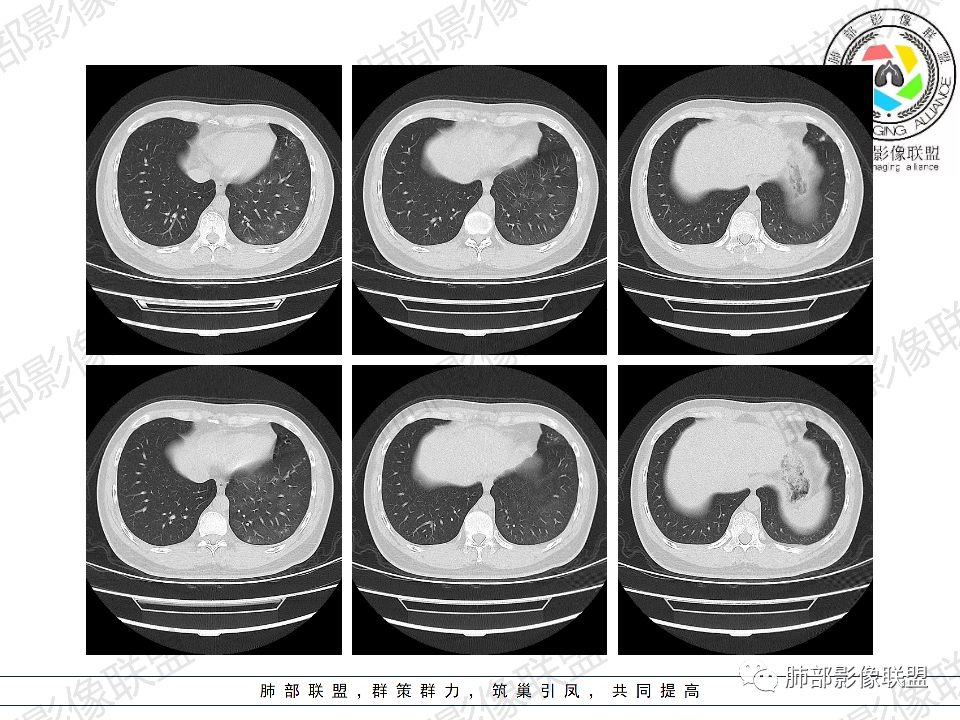

年轻男性,有HIV病史,免疫力缺陷病史,CD4明显减低,左肺胸膜下多发大小不等结节影,部分侧向融合,平行于胸膜,周围伴有模糊的GGO,部分结节与血管相连,血管束增粗,考虑隐球菌,建议查隐球菌荚膜实验,脑脊液隐球菌荚膜,鉴别:CMV(局限性比较少见)

年轻人,男性,HIV阳性,双肺多发斑片状,结节状阴影,以胸膜下分布为主,病灶与支气管血管束垂直生长,周围可见磨玻璃影,考虑肉芽肿病变,隐球菌感染可能性大,鉴别GPA,胞子菌肺炎。

双肺胸膜下多发大小不等结节伴晕征,部分似有融合

左肺多发大小不等结节影,部分融合,胸膜下分布为主,平行于胸膜,周围伴有磨玻璃晕,考虑隐球菌,鉴别:PJP

年轻男性,HIV阳性,胸闷喘憋,双肺胸膜下多发斑片结节影,周围伴晕,部分融合,白细胞低,CD4明显减低,考虑机会性感染性病变,隐球>PCP>结核

青年男性,HIV阳性,白细胞及淋巴细胞显著降低,CRP增高,胸闷气喘一周,影像为双肺胸膜下平行于胸膜分布的多发大小不等结节伴晕,单从影像上看,隐球是要首先考虑,但是不好解释临床症状。需要鉴别:1、曲霉所致IPA,临床有粒缺基础,胸闷一周要考虑,但影像不是典型的血道或气道分布又存疑,2、马尼,CD4低,HIV基础,要考虑,但是否有旅广史?另外纵隔淋巴结无肿大,肝脾不肿大,可能稍小。3、PCP,HIV基础,CD4低,胸闷气喘要考虑,影像分布不典型。4、腺病毒或EB病毒感染,HIV基础,影像改变要考虑,但是发病无发热,存疑。5、结核,临床与影像均不典型。可能小。综上,隐球>曲霉>PCP>马尼>病毒感染。下一步,查隐球荚膜抗原,NGS找病原体。

我们科里读片的时候,也是觉得主诉特别像PCP的主诉。但是影像学表现,双肺胸膜下多发小结节,结节周围带晕,蘑菇兄弟手拉手,有的结节侧向融合整体与胸膜平行。影像符合隐球。我们科里艾滋合并隐球菌真正确诊出来的很少。所以要说总结HIV合并隐球的病例特点,我没有发言权

肺隐球菌多分布在肺野外带或胸膜下区域,下叶多见,可能余隐球菌更容易在胸膜下肺泡中定植或蔓延有关;显示腺泡结节,然后取决于宿主免疫,可以入血,然后血播

2、类型:常见有孤立肉芽肿型、肺炎实变型、混合型(多发结节/实变/空洞)、弥漫粟粒/间质型。免疫正常宿主多表现为孤立肉芽肿型,也可以表现为肺炎实变型或混合型。免疫缺陷宿主则容易肺内播散形成多发(结节、实变、空洞)或弥漫粟粒/间质型,可累及中枢系统并发隐球菌脑炎。

5、分布:病灶分布多位于胸膜下,可紧贴胸膜,也可与胸膜邻近,病灶长轴与胸膜平行。(划重点,分布特点非常重要)

8、晕征:病变早期可出现磨玻璃晕征,为周围炎性渗出或肺间质受累。

9、坏死:可无坏死,也可凝固性坏死,出现空洞,空洞可规则光整呈类圆形,也可以为不规则厚壁,或出现“鬼脸征”。

10、“葫芦兄弟”:邻近胸膜多发结节,形态密度类似,可簇状分布,较少多形性,没有新旧不等。